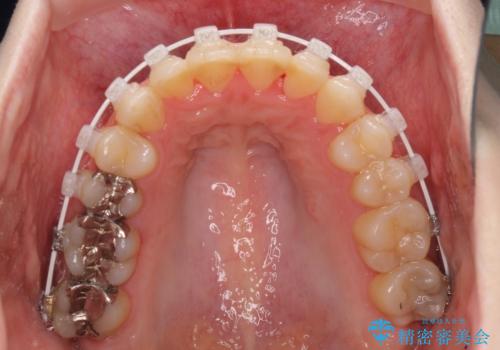

前歯のデコボコを改善 目立たないワイヤー矯正

- 前歯のデコボコを気にして来院された患者様です。

下顎が骨格的にずれており、上下正中を合わせることは難しいことが予想されたため、デコボコの解消を主目的として、ワイヤー矯正を行うこととしました。